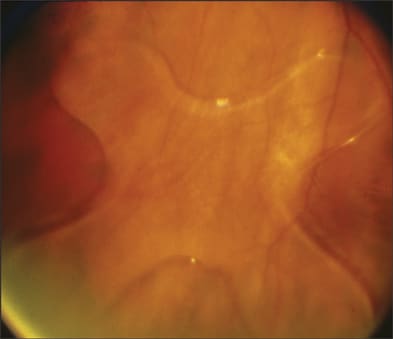

The management of a dislocated IOL depends on various factors, including the patient's ocular and general health, as well as specific considerations regarding the anatomy of the affected eye (Table 2). In patients who are poor surgical candidates and have good visual function in the fellow eye, observation of a dislocated IOL in the vitreous cavity may be a reasonable option. In this setting, contact lens correction can be considered, although aphakic spectacles may be used in monocular patients. In one such series of patients with older IOL styles (such as Copeland and Binkhorst lenses) that were observed, 60% maintained visual acuity of 20/40 or better, and 13% developed RD over an average of 3 years of follow-up (Figure 1).5

Figure 1. Dislocated Copeland-style intraocular lens on the retinal surface.